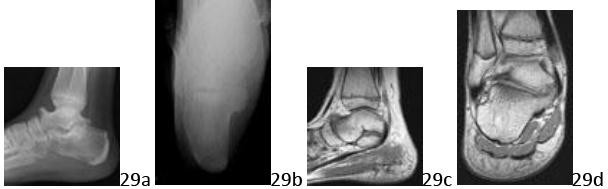

10. # 29a 29b 29c 29d A 13-year-old boy has had a 12-month history of stiffness with worsening right hindfoot and ankle pain. Examination reveals normal ankle motion but there is decreased subtalar motion. Radiographs are shown in Figures 29a and 29b and MRI scans are shown in Figures 29c and 29d. What is the most likely diagnosis?

DISCUSSION: The patient's history and studies are consistent with a talocalcaneal coalition. The lateral radiograph shows talar beaking and a positive "C" sign; however, the axial view does not show the classic sloped medial facet that can be seen with a bony talocalcaneal coalition. The MRI views are consistent with a fibrous coalition of the medial aspect of the posterior facet with subchondral edema. There are no signs of any other coalitions. Whereas the talar beak is large and the studies show the medullary canal is in continuity with the lesion, the other findings are more consistent with a coalition than an osteochondroma, which would also tend to have an irregular appearing surface. There is no periarticular osteopenia or hyperemia consistent with an inflammatory arthropathy. The Preferred Response to Question # 29 is 2.